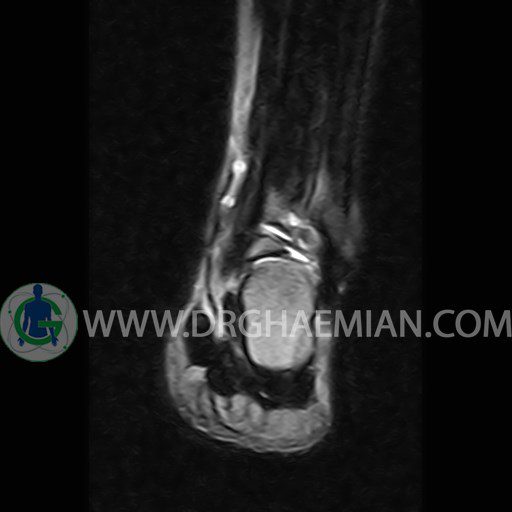

ام آر آی پا یک روش تصویربرداری از پا است که با استفاده از آهنرباهایی قوی تصاویری از پا ایجاد می کند. این تصاویر شامل قوزک، ساق پا و بافت های پیرامون آن ها می شود. ام آر آی از تشعشعات استفاده نمی کند. در این کیس گیرافتادگی خلفی مچ پا، سینوویت گذرا و کبودی استخوان دیده می شود.

LEFT ANKLE MRI

(Without contrast)

Technique :Axial T2 , coronal , sagittal T1 and T2 ,sagittal T2 fat sat .

The bones comprising the ankle joint show normal position and configuration.

The joint space is of normal width.

The cortex shows normal thickness and smooth contours , especially along the tibiotalar articular surfaces.

The lateral and medial ligaments are normal in their course , width and signal characteristics.

The achilles tendon is normal in its course , width and signal characteristics and the preachilles fat is clear.

Tarsal sinus is normal in shape and signal intensity.

– Mild effusion in tibio – talo – calcaneus joint suggestive for transient synovitis

– Bone bruise in tibial insertion of talus

– Elongated lateral tubercle of talus ( stieda process ) with adjacent soft tissue swelling & edema in the retrocalcaneals bursa suggestive for posterior impingement

are seen